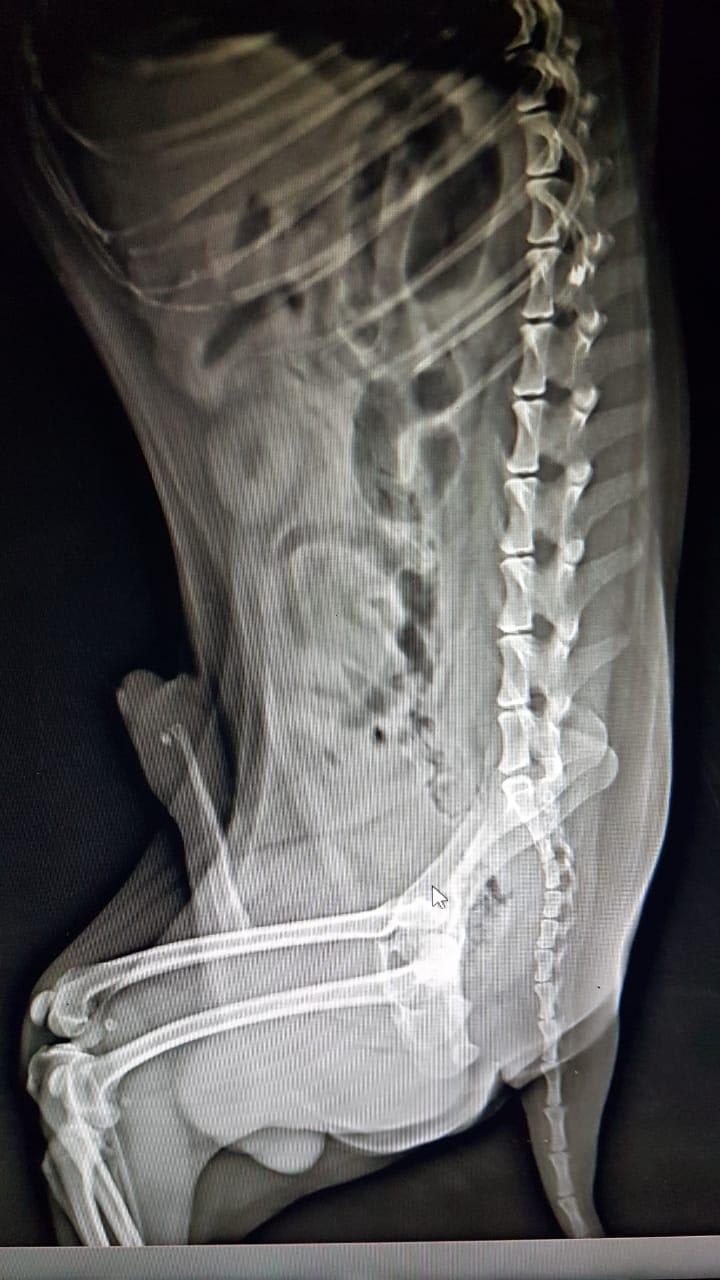

My dog has a urolith in his urethra. Is this a serious problem?

Thank you for submitting your question regarding Teddiee. He appears to have a small urolith (stone) in his urethra. This can make it difficult for him to urinate properly. I hope this information helps!